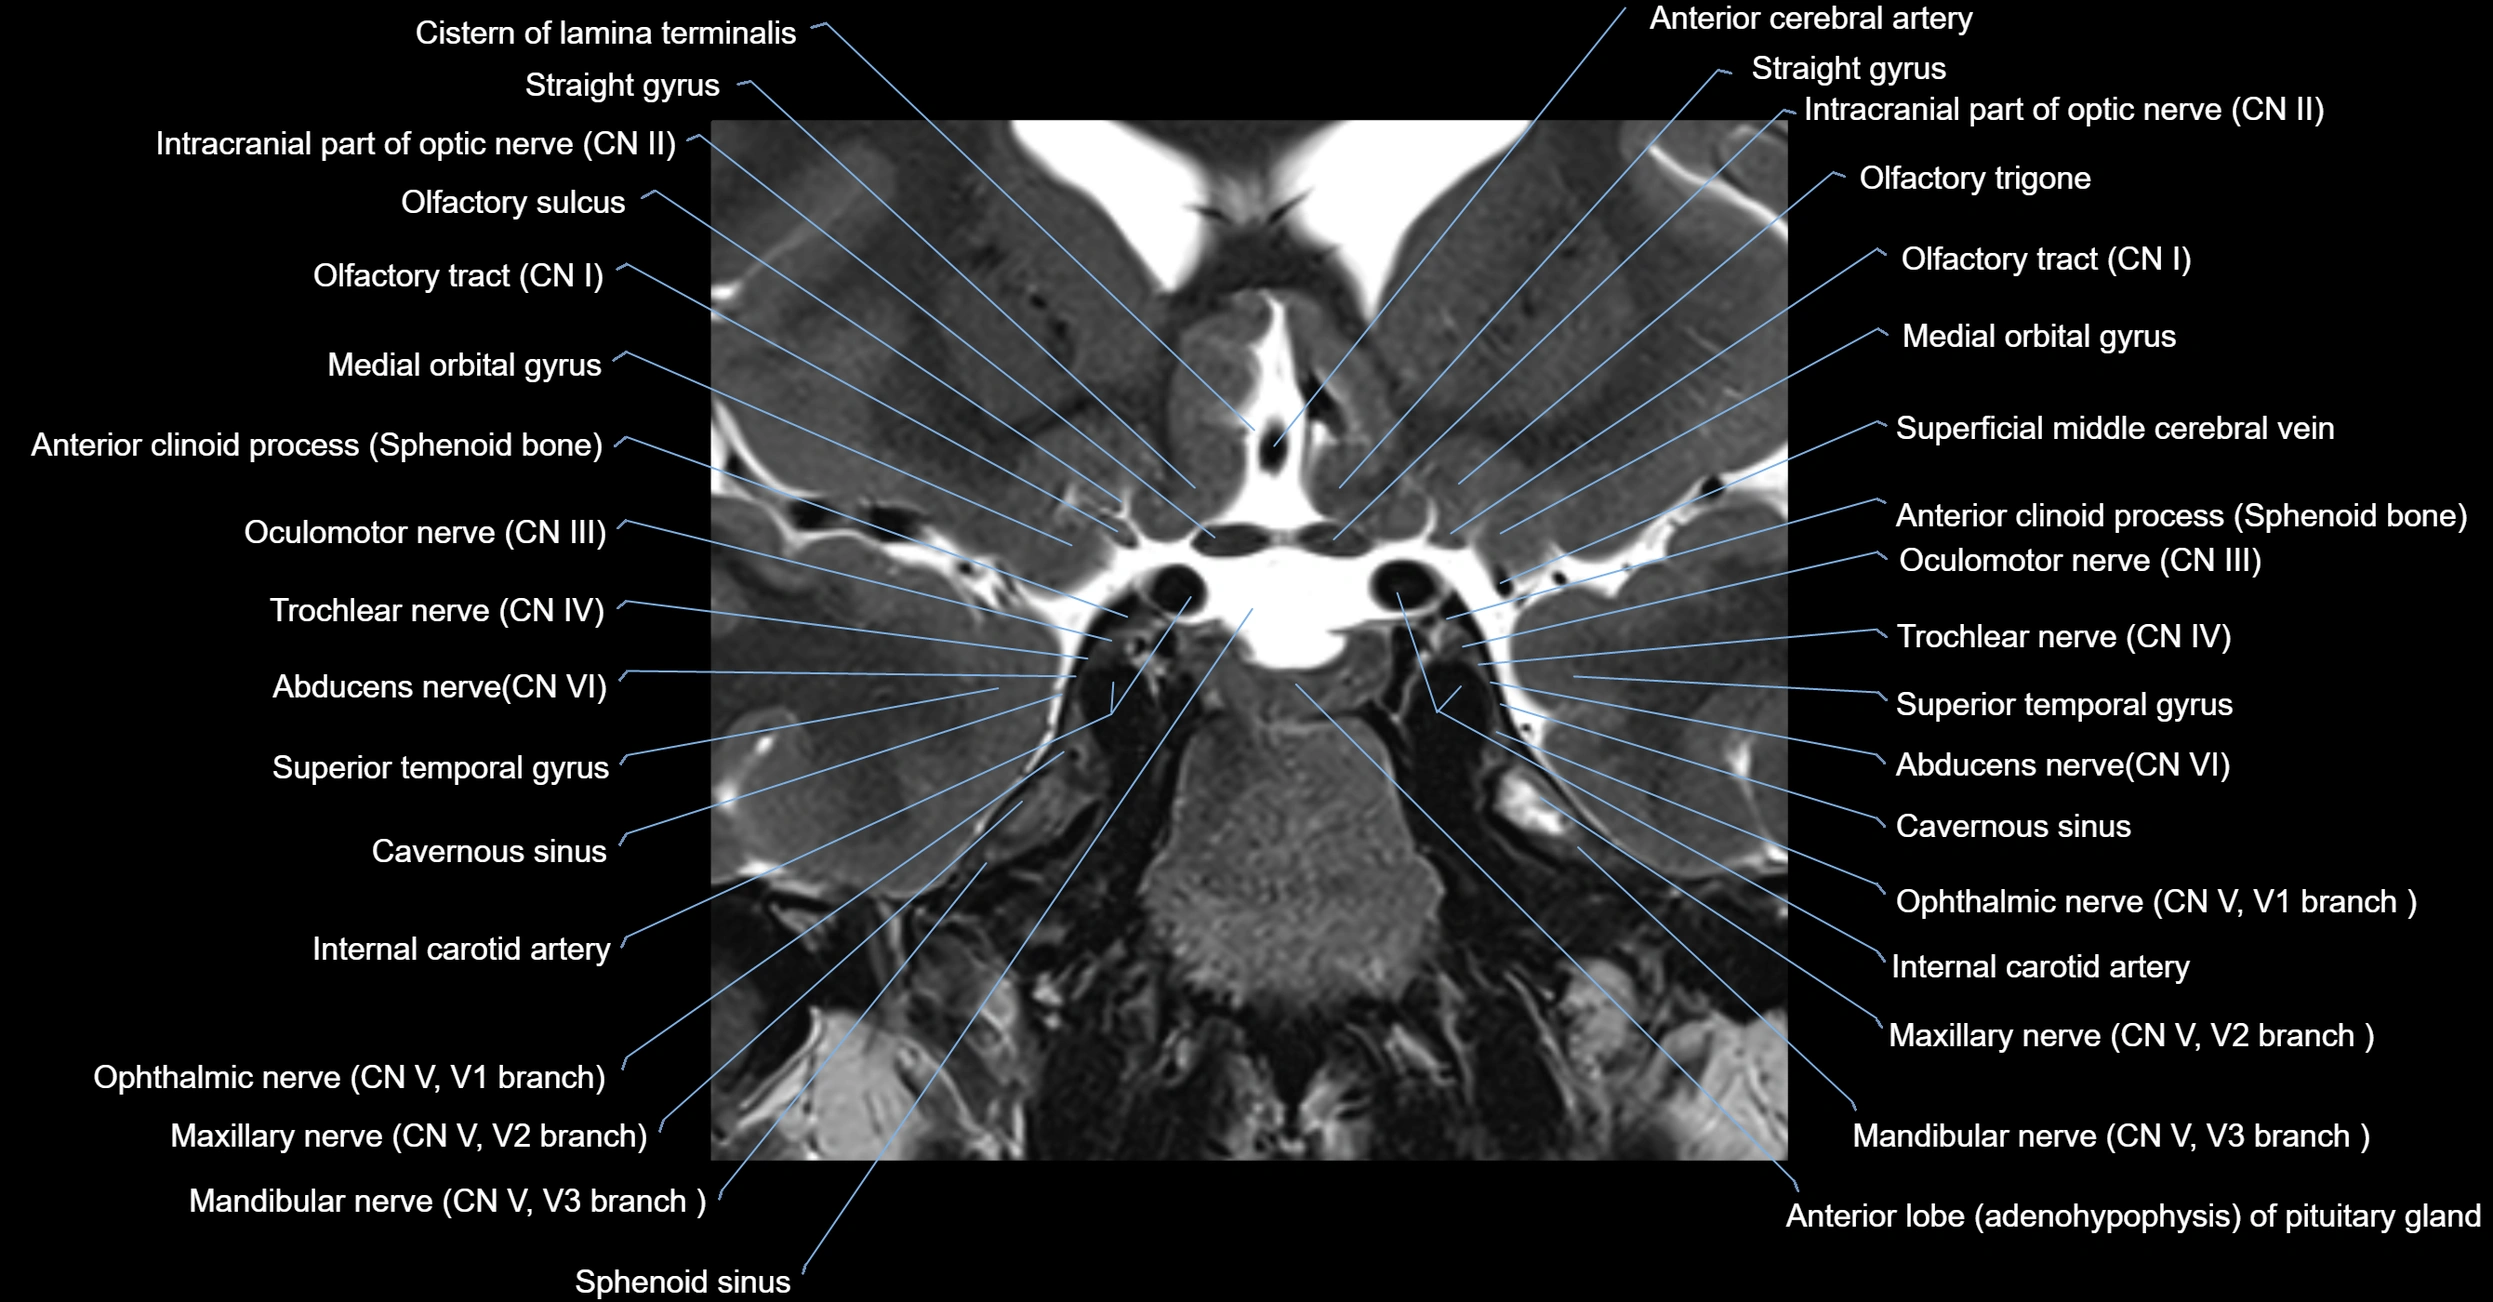

MRI Appearance

-

The abducens nerve is a small, thin, linear structure

Best visualized on high-resolution T2-weighted 3D MRI sequences (e.g., FIESTA or CISS)

Seen as a hypointense (dark) line running from the brainstem at the pontomedullary junction, traversing the prepontine cistern, and entering Dorello’s canal under the petrosphenoidal ligament, then into the cavernous sinus, and finally the orbit

May be challenging to visualize in standard MRI due to its small size

Pathology may be inferred by absence, displacement, or enhancement of the nerve

MRI images